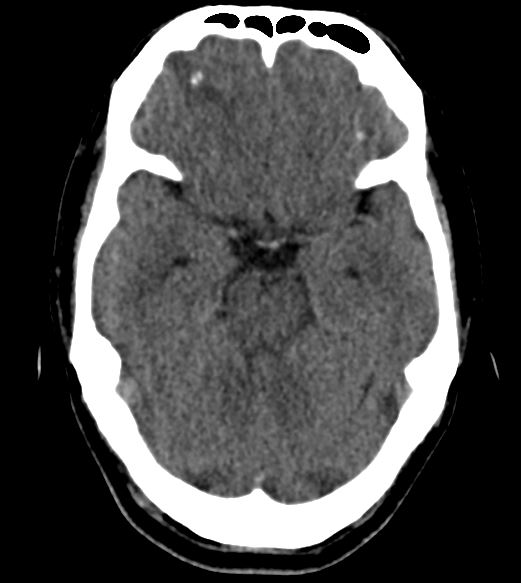

A young Indian national presented with his first ever episode of generalized tonic-clonic seizures and was hospitalized. He was previously healthy, vegetarian, and had been based in Singapore for the past 3 years, working in the construction industry. A plain CT head performed at the emergency department showed a spot of calcification at the right frontal lobe with surrounding oedema.